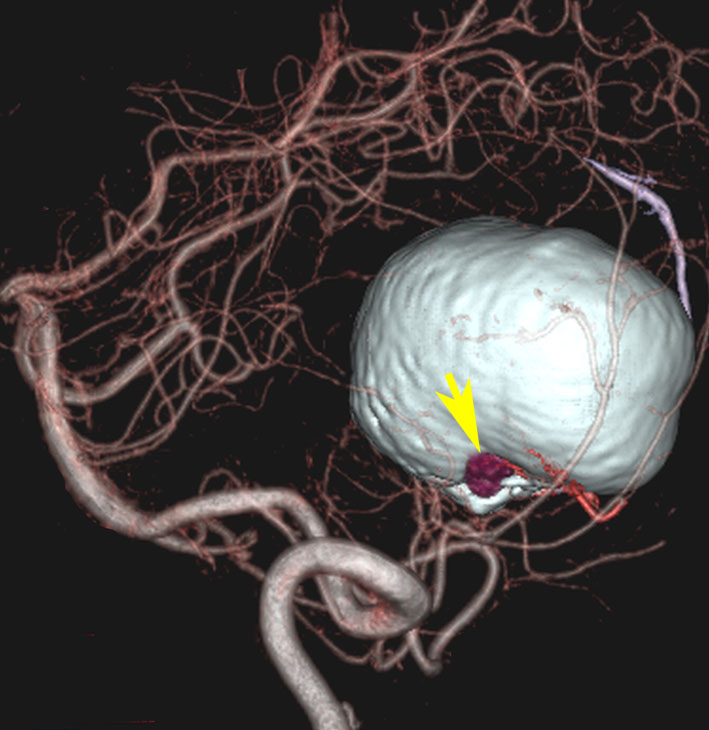

左小脳にできた小さな のう胞性血管芽腫です。矢印の先にある小さな塊だけが腫瘍で周囲は腫瘍から染み出した液体が溜まっています(のう胞といいます)。右側は血管撮影とMRIを組み合わせた画像で,腫瘍に動脈が流入しているのが見えます。

これも血管芽腫です。おそらく小脳発生なのでしょうが,延髄の両側に強く癒着していて延髄の血管も腫瘍の中に入っていて,腫瘍血管には動脈瘤も合併していて破裂しました。この腫瘍を摘出するのは不可能にも思えましたが,無事にできました(下の写真)。患者さんも私もへとへとになりました。 でも,このような血管芽腫の手術はうまく行くとは限りません,手術不可能と考えた方がいいかもしれないと今でも思っています。手術すると決めればものすごく高いリスクを患者さんも外科医も背負うことになります。放射線治療をして治るサイズではないので他に治療法はありませんが (>_<) 大きな血管芽腫を手術する提案をされたら,少なくとも執刀医の経験数は尋ねましょう。

フォンヒッペルリンドウ病に合併した大きな右小脳半球血管芽腫です。大きなものでは静脈環流障害(鬱滞)のために脳浮腫を来すことが多いし,その分,手術時の静脈圧が高くて止血が難しいと考えなければなりません。水頭症を呈して症状は重篤でしたが,右後頭窩開頭で比較的簡単に全摘出できて回復しました。小脳半球に生じるものは手術で大きな障害を残すことはほとんどなく術後の症状症状の回復も順調なことが多いです。

同じ患者さんです。上記の手術の5年後に新たな血管芽腫が激しく増大しました。これは小脳虫部なので両側の上小脳動脈がfeeding arteryとなります。bilateral occipital transtentorial approachという特殊な手術方法でしか摘出できません。幸いこの腫瘍も無事に全摘出できました。

真偽のほどは解りませんが頭の中で血液が流れる音がするというのが主訴です。その後に軽度の歩行失調と構語障害が出て発見されました。この程度のものでもAVMと同じように血管雑音を自覚することがあるのかもしれません。画像をよく見ると右の小脳扁桃のもので,延髄はただ圧迫されているだけです。血管芽腫はエリスロポエチンを産生して多血症になることがあるのですが,この患者さんは16.6 MIU/mlで正常値でした。

右のPICAが主たるfeeding arteryです。でもPICAのretromedullary segmentからshort feedersが流入していますから,油断をすると延髄背側障害という厳しい手術合併症を生じる可能性は十分あります。この腫瘍は正中後頭下開頭で全摘出できましたし,神経脱落症状を残していません。難易度は中等度のものです。